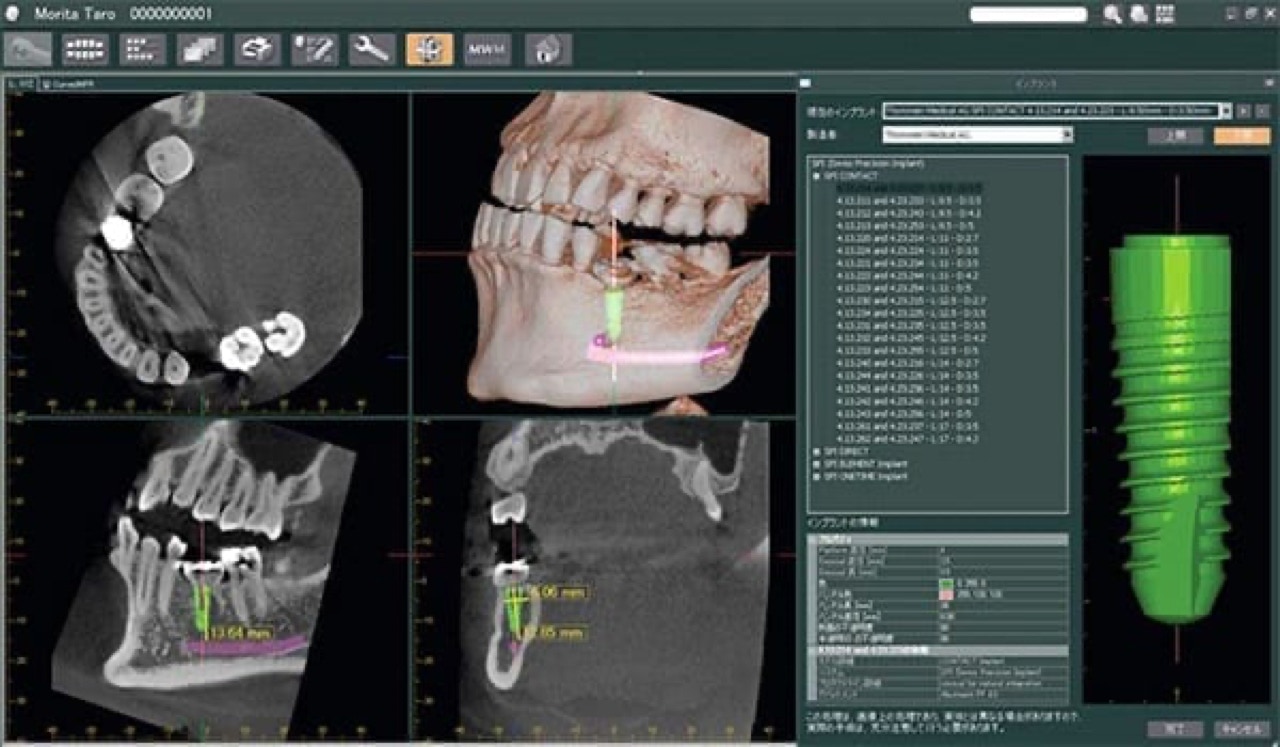

Unser praxiseigenes 3D Rötgengerät (DVT) ermöglicht eine präzise Implantatplanung vor Ort ohne zusätzliche Wege zu Überweisern.

3D Röntgen mit digitaler Volumentomographie (DVT)

Durch unsere digitale 3D Röntgenanlage können wir die Strahlung, der Sie ausgesetzt sind, im Vergleich zum konventionellen Röntgen um bis zu 90 % verringern.

Unser modernes Röntgen- und Computersystem ermöglicht es uns, die aufgenommenen Röntgenbilder sofort am Monitor darzustellen und zu bearbeiten. Das hohe Auflösungsvermögen  gewährleistet eine genaue und sichere Diagnose und gibt uns und Ihnen die Möglichkeit, anhand der Darstellung am Monitor gemeinsam eine exakte Behandlungsplanung zu erarbeiten.

Was habe ich durch das DVT 3D Röntgen für Vorteile?

Die Digitale Volumentomographie (DVT) ist ein hochmodernes dreidimensionales Röntgenverfahren. Diese Methode ermöglicht dem Zahnarzt, die Strukturen (z.B. Knochen, Zähne, Nervverläufe) im Kieferbereich dreidimensional zu betrachten und dadurch die vorgesehene Behandlung präzise zu planen.

Das DVT 3D Röntgen ermöglicht eine präzise Diagnostik: Die hochauflösenden 3D-Bilder liefern ein sehr genaues Abbild der knöchernen Strukturen, der Zähne und Zahnwurzeln. Eingriffe, wie Implantationen, können exakt geplant werden und Nervverletzungen vermieden werden.

Auch bei unklaren Beschwerden kann das DVT helfen. Zähne und Zahnwurzeln können dreidimensional dargestellt und von allen Seiten "beleuchtet" werden. So können Prozesse sichtbar werden, die beim herkömmlichen Röntgen von anderen Strukturen verdeckt werden.